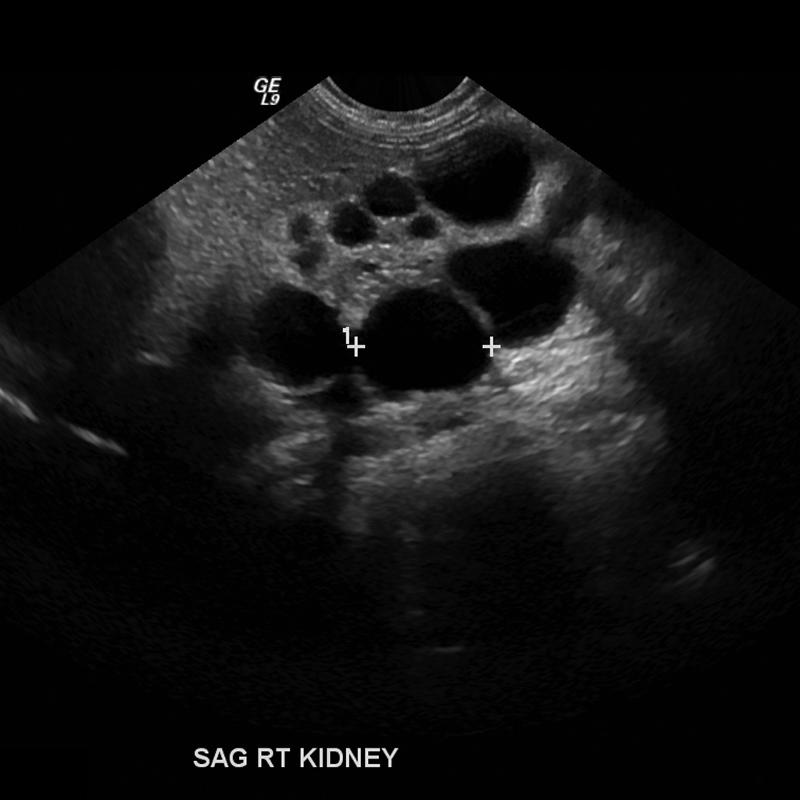

often seen with hydronephrosis in the upper pole

Duplex Kidney

Seen in 15% of population

Duplex Kidney